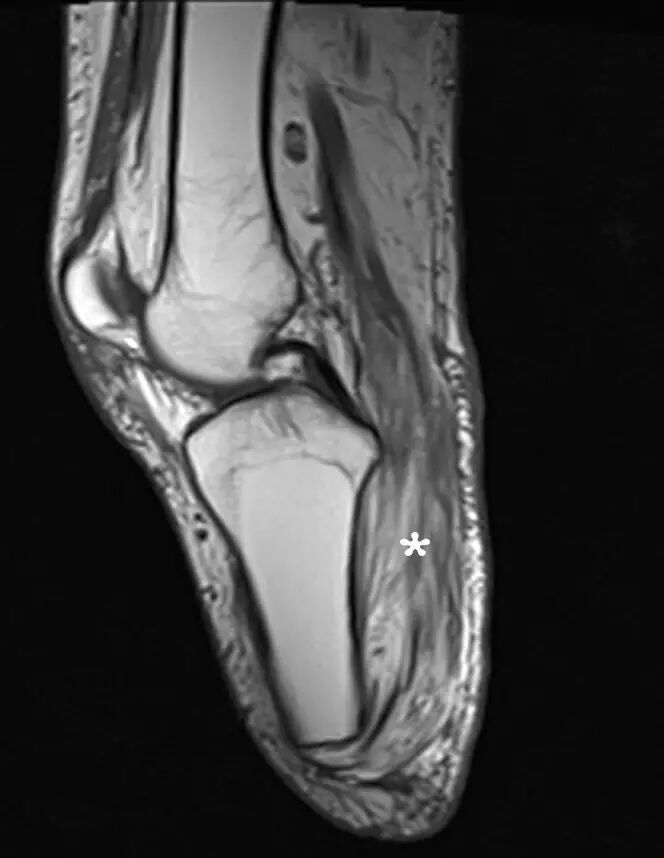

图15.一个43岁的男性,在12年前的一次摩托车事故后,膝下截肢的慢性废用。 矢状T1加权磁共振成像显示增加的信号,表明腓肠肌和腘肌(星号)的脂肪浸润。

![]()